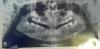

фиона Опубликовано 17 декабря, 2009 Поделиться Опубликовано 17 декабря, 2009 Мне 19 лет у меня молочные клыки сделала снимок и увидела что над ними ЛЕЖИТ горизонтально ростущий зуб,была у ортодонта она мне сказала сделать ортопантомограмму (что то такое почерк не понятен),и добавила что будем удалять молочные клыки и ставить брекеты.Обязательно ставить брекеты?????очень бы не хотелось и вообще я не понимаю для чего их нужно ставить на все зубы если проблема только с клыками?????????????? Ссылка на комментарий

Премоляр Опубликовано 18 декабря, 2009 Поделиться Опубликовано 18 декабря, 2009 Мне 19 лет у меня молочные клыки сделала снимок и увидела что над ними ЛЕЖИТ горизонтально ростущий зуб,была у ортодонта она мне сказала сделать ортопантомограмму (что то такое почерк не понятен),и добавила что будем удалять молочные клыки и ставить брекеты.Обязательно ставить брекеты?????очень бы не хотелось и вообще я не понимаю для чего их нужно ставить на все зубы если проблема только с клыками??????????????Отлично...Теперь по делу-бкекеты необходимы для опоры при вытяжении ретенированных клыков.(вы говорите что горизонтально лежит),и для нормализации положения остальных зубов(наверняка есть повороты и наклоны,кот.образовались из-за ретенции клыков). Это все,что можно ответить не видя ни одной фотки.П.С. Выклдывайте хотя бы панорамку Ссылка на комментарий

Force Опубликовано 19 декабря, 2009 Поделиться Опубликовано 19 декабря, 2009 капец суставу....Хотя данных практически нет. Но судя только по этому снимку потребуется не просто лечение, а полная реконструкция прикуса. Причем удаление всех восьмых - необходимый минимум. Ссылка на комментарий